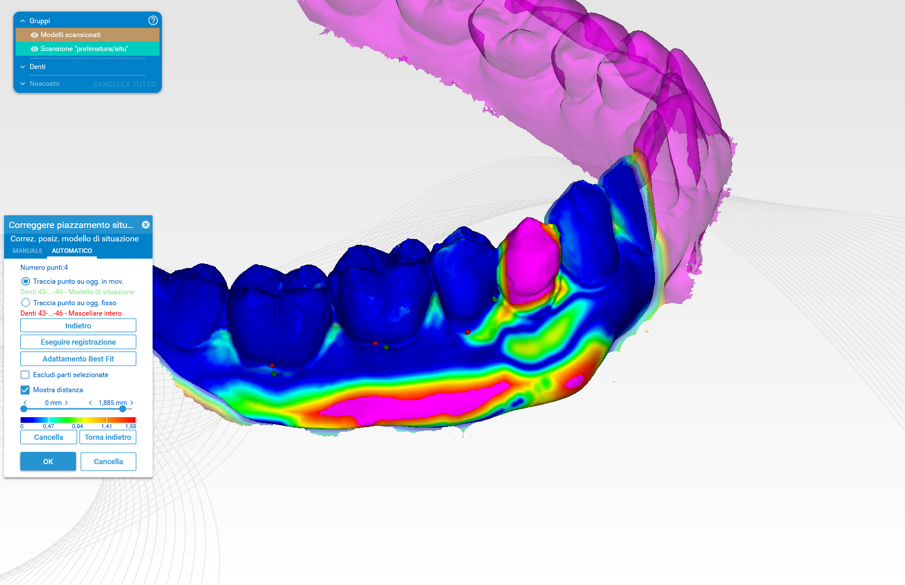

Ogni gruppo di scansione per ogni paziente è stato elaborato tramite exocad e analizzato confrontando S0 con S1 (valutazione a tre mesi) e S0 con S2 (valutazione a un anno) (Figg. 11, 12). La valutazione del perimetro di interesse riguarda una zona trapezoidale situata nella parte innestata che si dilata da un’ipotetica linea di congiunzione dei margini dei denti adiacenti e si estende fino alla linea mucogengivale e lateralmente alle aree interprossimali.

Attraverso l’analisi visiva colorimetrica si è potuto valutare l’incremento volumetrico ai differenti time-points: gli STL ottenuti sono stati analizzati con il software Rhinocerus per l’analisi delle variazioni numerico-volumetriche vestibolari. I dati sono ancora in fase di analisi e in questa parte dello studio è stata presa in considerazione solo l’analisi colorimetrica in un range compreso tra 0 e 2 mm8.

Il gruppo di confronto S0 con S1 (Fig. 11) presenta un aumento lineare che si attesta nell’intervallo tra 0 e 2 mm con zone all’interno dell’area di interesse di colore verde-arancio-rosso. Tale risultato è presente in tutti e 10 i casi analizzati. Nel gruppo di confronto S0 con S2 a distanza di un anno (Fig. 12), vi è un rimodellamento della zona innestata ma con un aumento rispetto la baseline (S0) compresa tra 0 e 1,5 mm, ovvero con zone all’interno delle aree di interesse di colore blu-azzurro-verde. Tale risultato è presente in tutti e 10 i casi analizzati.

L’analisi dei risultati si è basata sulla scala colori con intervallo compreso da 0 a 1,885 mm rispettivamente con scala colori da blu a rosso (Fig. 12).